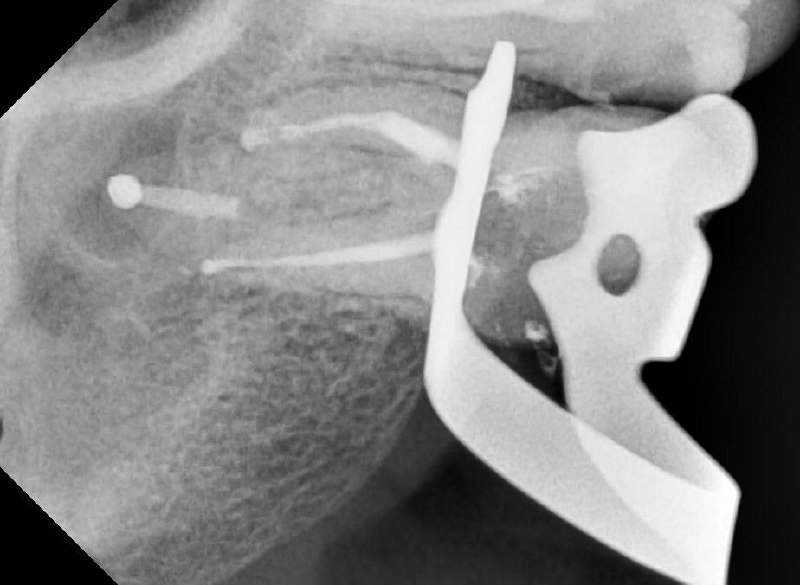

📸 На фото представлен клинический случай. Пациент обратился в нашу клинику с жалобой на боль при надкусывании 😬. При первичной диагностике был выявлен сломанный инструмент в корневом канале, который привёл к воспалению 🦠.

На следующих снимках видно, что отломок инструмента был успешно извлечён. Все каналы были пройдены, механически обработаны под микроскопом 🔬 и запломбированы.

Работа врача -стоматолога -микроскописта Овчинниковой М.И